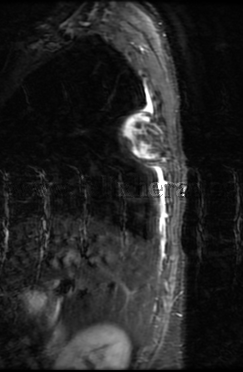

Tumor de mediastino posterior

Neuroma